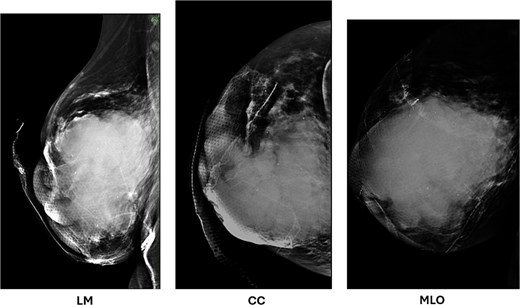

Her workup was expedited given the expected diagnosis of malignancy, with the differential diagnosis including a neoplasm arising from breast tissue that had ulcerated, or an advanced squamous cell carcinoma. Ultrasound of her right breast and a diagnostic mammogram were performed that noted a mixed solid/cystic BI-RADS 5 lesion within the right central breast with extension to the nipple (Fig. 2). There were no abnormal lymph nodes appreciated on breast imaging. A CT of the chest, abdomen, and pelvis was obtained for staging which showed multiple stable sub-6 mm nodules in the left lung, <1 cm mediastinal and hilar lymph nodes, and multiple additional suspicious nodes in the right axillary, supraclavicular, and neck chains. A bone scan was obtained to complete the staging workup, which did not show any evidence of osteoblastic metastatic disease. A core needle biopsy of the solid component demonstrated ‘invasive malignant squamous cells surrounded by cellular, spindled, and proliferative stroma in an inflammatory background’. The lesional cells were highlighted with p63, CK5/6, and GATA3, and were negative for desmin, SMA, SOX10, and CD34. Mucicarmine showed focal intracellular mucin. AE1/AE3 was used to evaluate the presence of carcinoma in sentinel lymph nodes obtained during upfront surgery. Cytology was obtained from the cystic component that was concordant with pathologic findings from the core needle biopsy (Fig. 3).

Diagnostic mammogram of the right breast demonstrates a mixed solid and cystic lesion in the central breast (BI-RADS 5), with extension to the nipple.